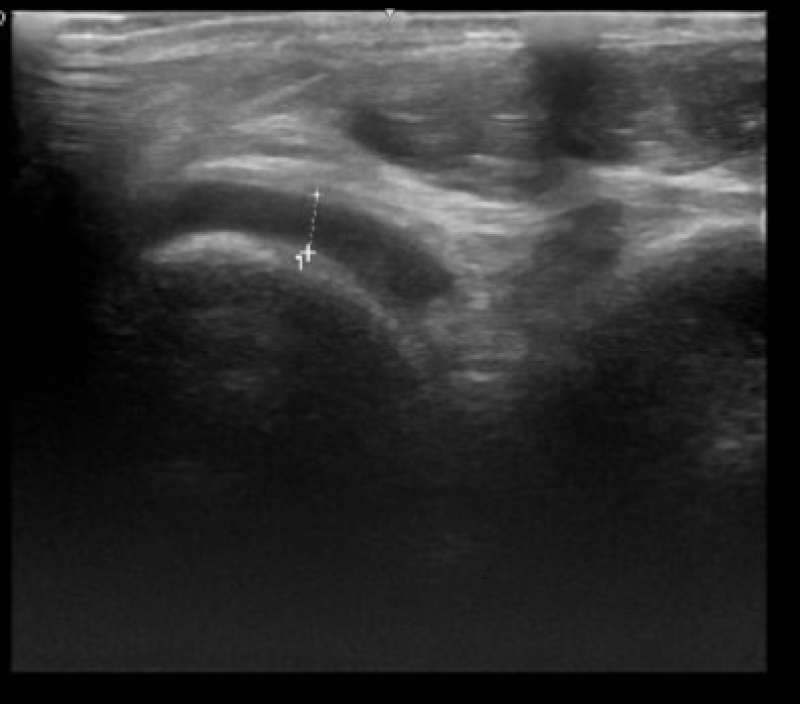

ประเทศเวียดนาม อายุเพียง 22 ปี งมีอาการปวดข้อเท้าซ้ายอย่างรุนแรง โดยก่อนหน้านั้น 1 วัน เขาเริ่มมีอาการปวดแบบหน่วงๆ และรุนแรงขึ้นในเวลากลางคืนหรือขณะเดินจนไม่สามารถเดินได้เอง ผลตรวจทางห้องปฏิบัติการพบว่ามีกรดยูริกในเลือดสูงผิดปกติ ไขมันในเลือดผิดปกติ (คอเลสเตอรอลและไตรกลีเซอไรด์สูง) มีของเหลวในข้อเท้าซ้าย ไขมันพอกตับระดับ 2 และพบติ่งเนื้องอกในถุงน้ำดี